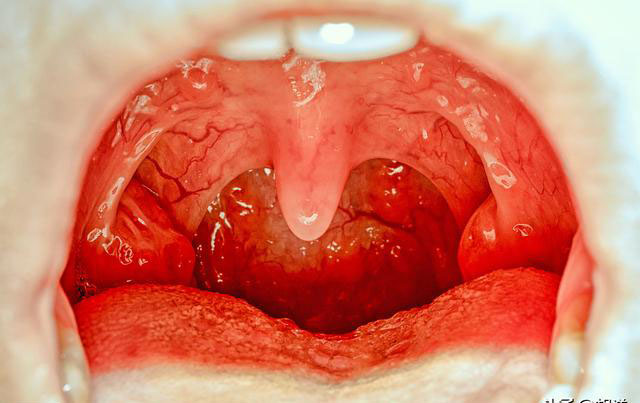

扁桃体癌

扁桃体癌的症状是什么?不定期刷牙或用牙线剔牙.有人乳头瘤病毒感染.

不要小看扁桃体炎尤其是反复发作的化脓性扁桃体炎扁桃体癌症状有哪些